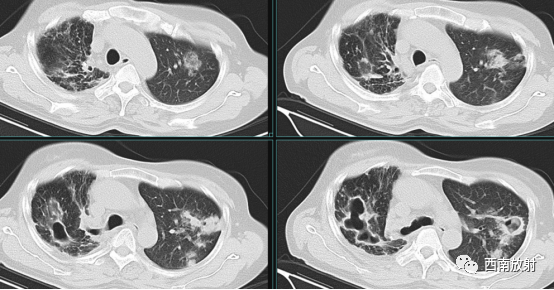

▲女,66 岁,鸟分枝 杆菌肺病,右肺上叶支气管扩张伴多发小叶中心结节(树芽征)

▲男,79 岁,脓肿分枝杆菌肺病,两肺多发支气管扩张伴小叶中心结节( 树芽征)

胞内分枝杆菌组中,支气管扩张CT征象的发生率仅次于小叶中心结节。鸟分枝杆菌组及脓肿分枝杆菌组中支气管扩张出现的比例差异无统计学意义。堪萨斯分枝杆菌组出现支气管扩张最少。